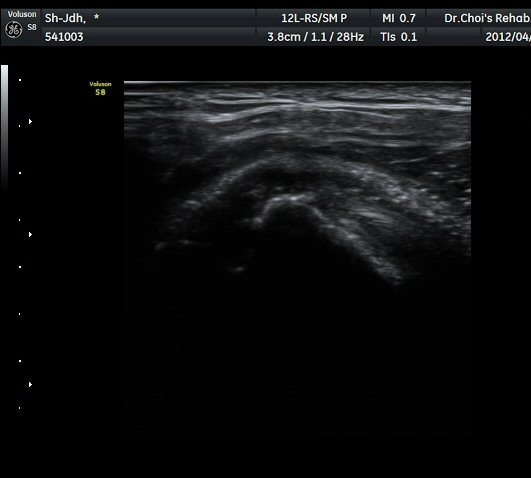

À̵ιڱ٠Ⱦ´Ü¸é°Ë»ç¿¡¼­ À̵ιڱٰÇÀÇ ºñÈĸ¦ º¸ÀÓ(»çÁø 1, 2).

À̵ιڱٰú ÀÌ¿ôÇÑ °ß°©ÇÏ±Ù°Ç »óºÎ¿¡¼­ ±¹¼ÒÀûÀÎ ¿¬°á¼º ¼Ò½ÇÀÌ °üÂûµÊ(»çÁø 3).